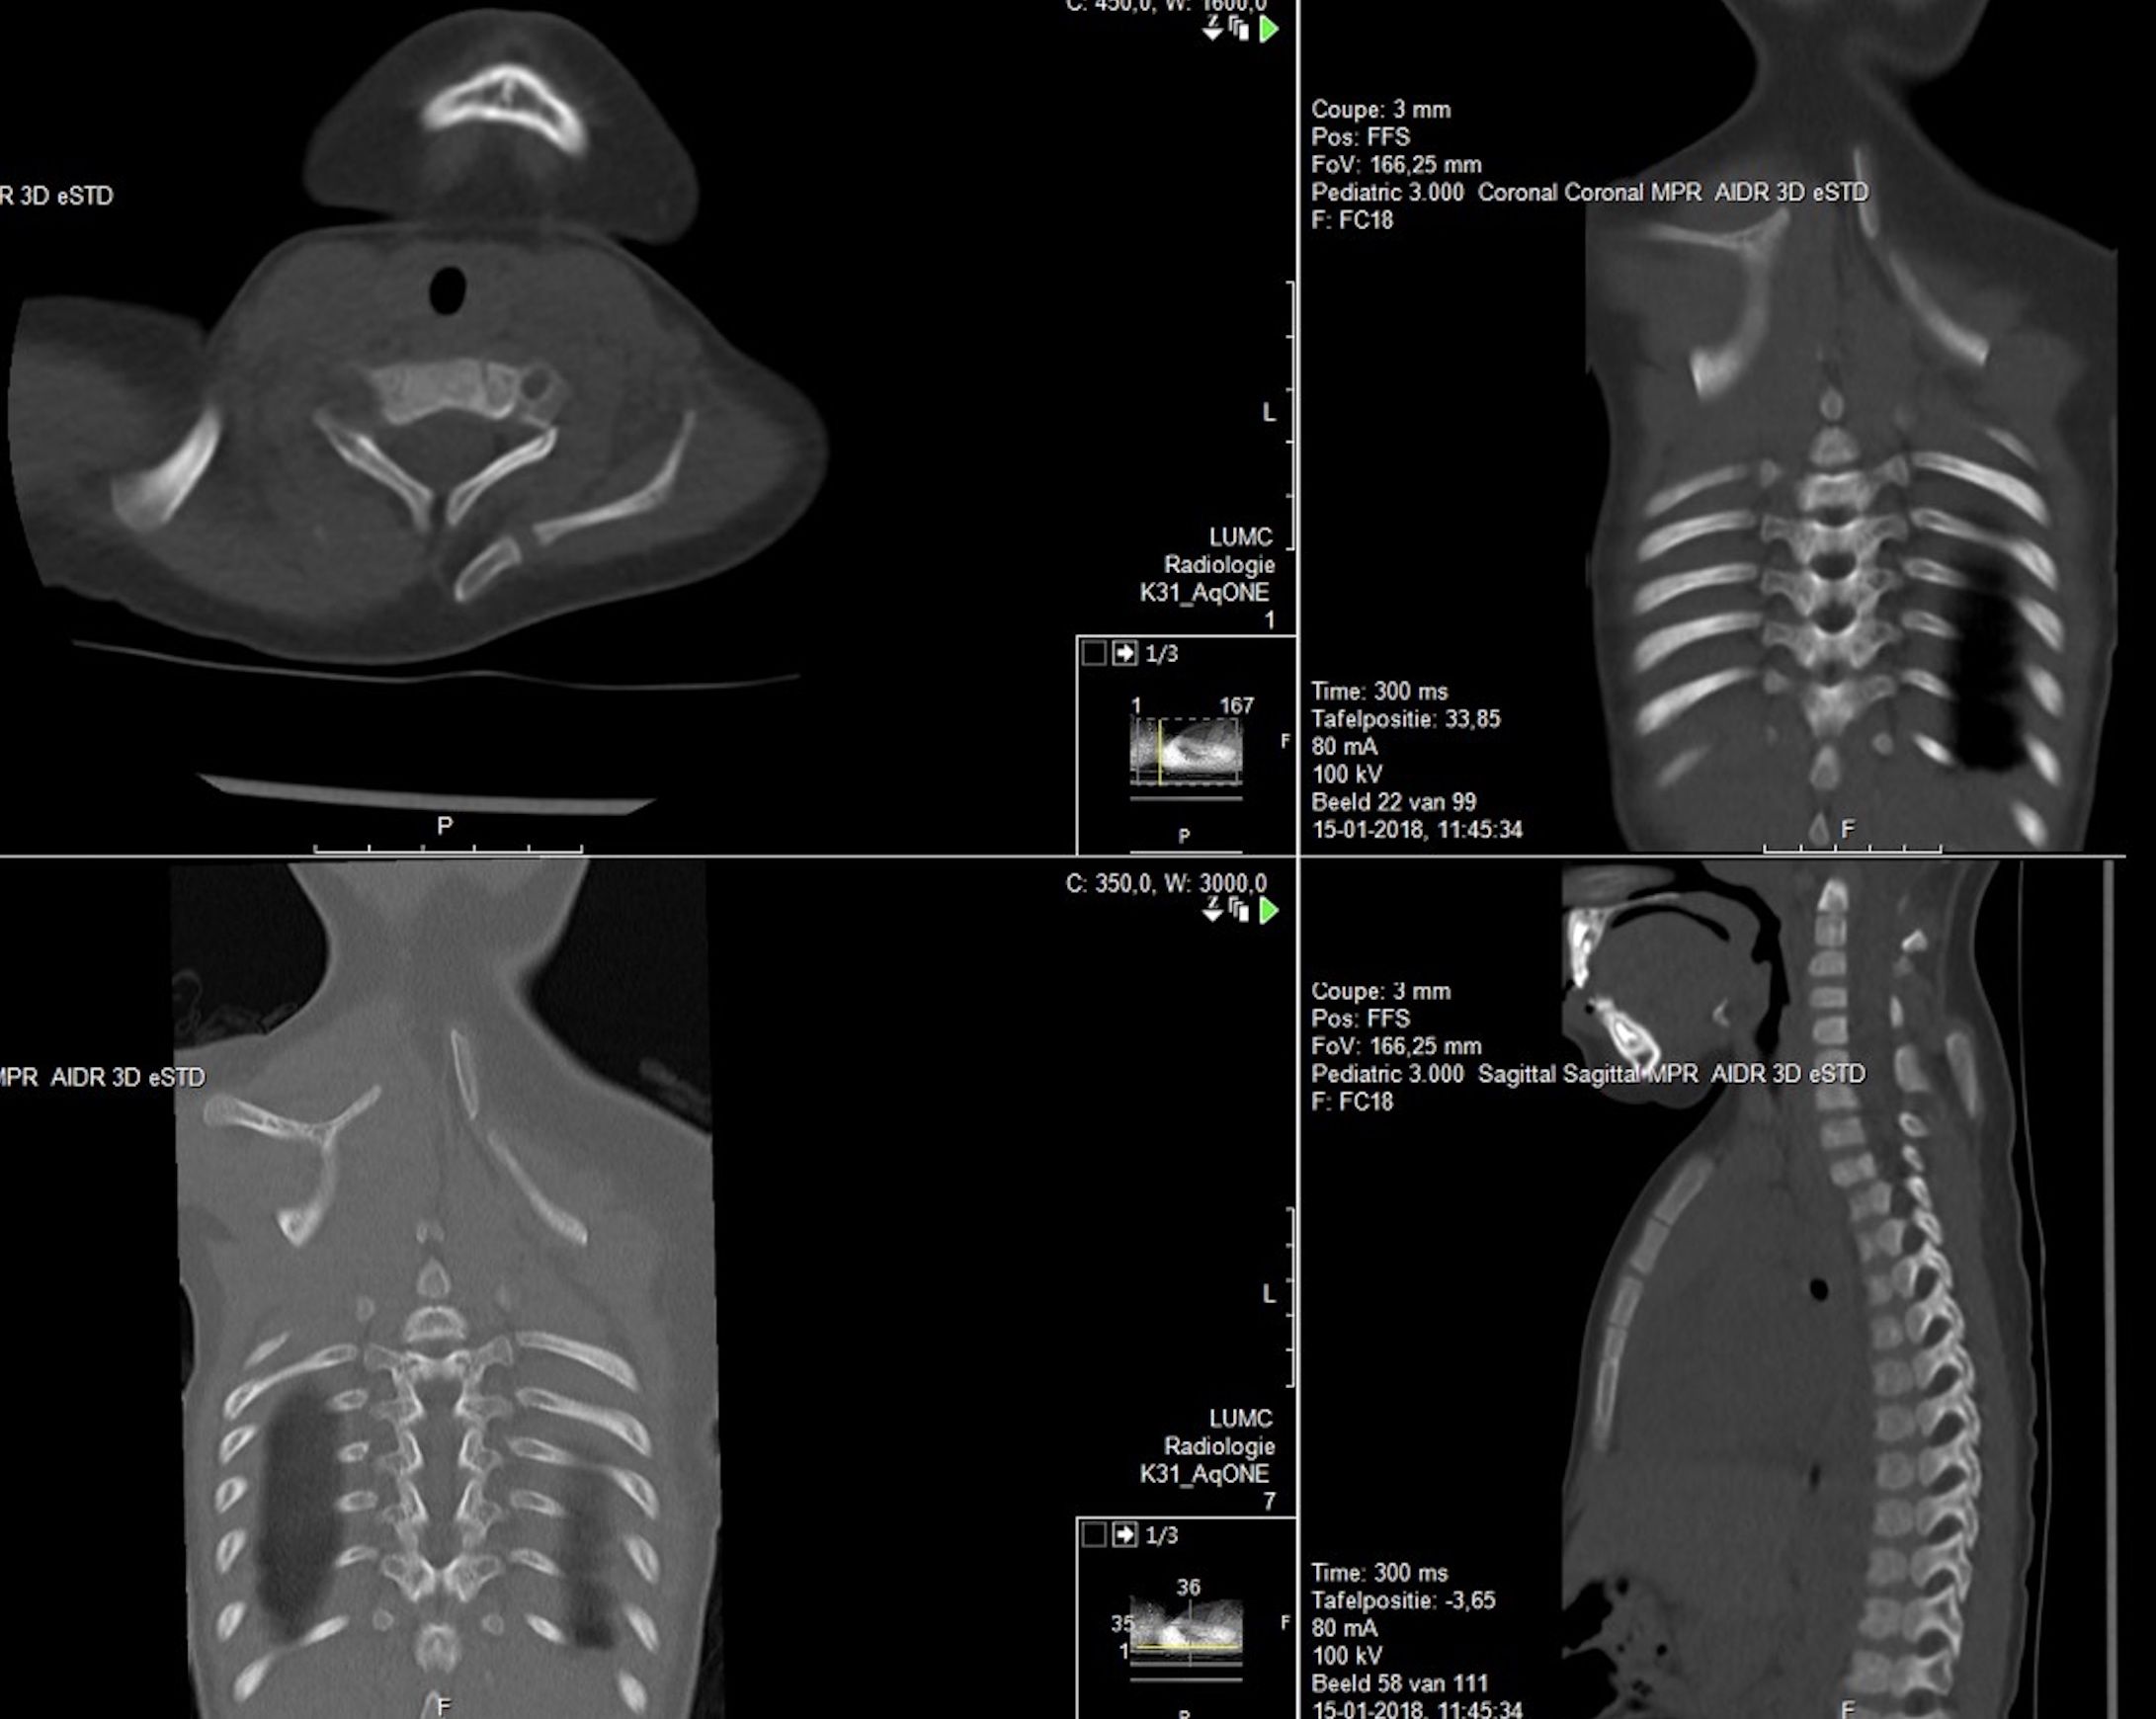

Subsequent radiographs and an ultrasound of both shoulders and scapulae and a close-up X-ray of the left shoulder revealed a fusion of costa 3 and 4. For further evaluation of the cervical spine we made a CT scan which showed a partial fusion of the vertebral corpus C5-C7 on the left and corpus Th2-Th3, Th5-Th6, a fork rib of the 4th rib on the right side (figure 2) and a different morphology of costa 7 on the right. Also seen was a bilateral Sprengel’s deformity; left grade 3 with os omovertebrale, right grade 2 (table 1), articulating with the spinous process C7 (figure 3). As a result of these findings the parents were informed about the diagnoses and the patient will be monitored by a paediatric orthopaedic surgeon until adulthood. Physiotherapy was continued with the aim of maintaining shoulder function. Clinical genetic research revealed no known associated gene mutations, but did show a sequence change in the GDF6 gene with unknown clinical consequences.

Figure 2. 3D reconstruction of CT thorax, cervical spine, shoulders.